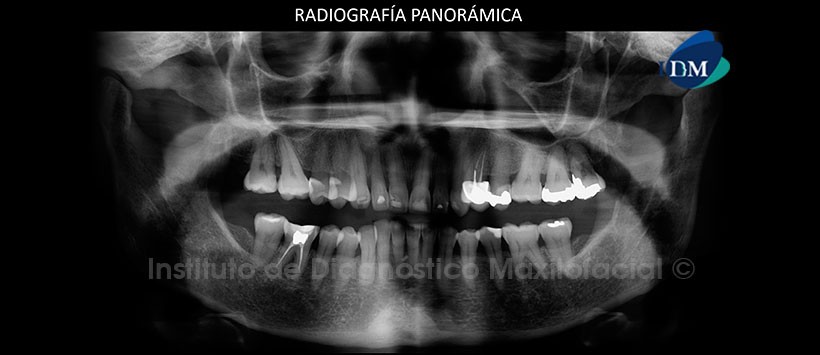

A la evaluación panorámica se aprecia a simple vista, un leve aplanamiento del contorno de ambos cóndilos mandibulares, apiñamiento dentario del sector anterior y anomalías dentarias en las piezas 12 y 22 compatibles con diente invaginados. (Figura 1)